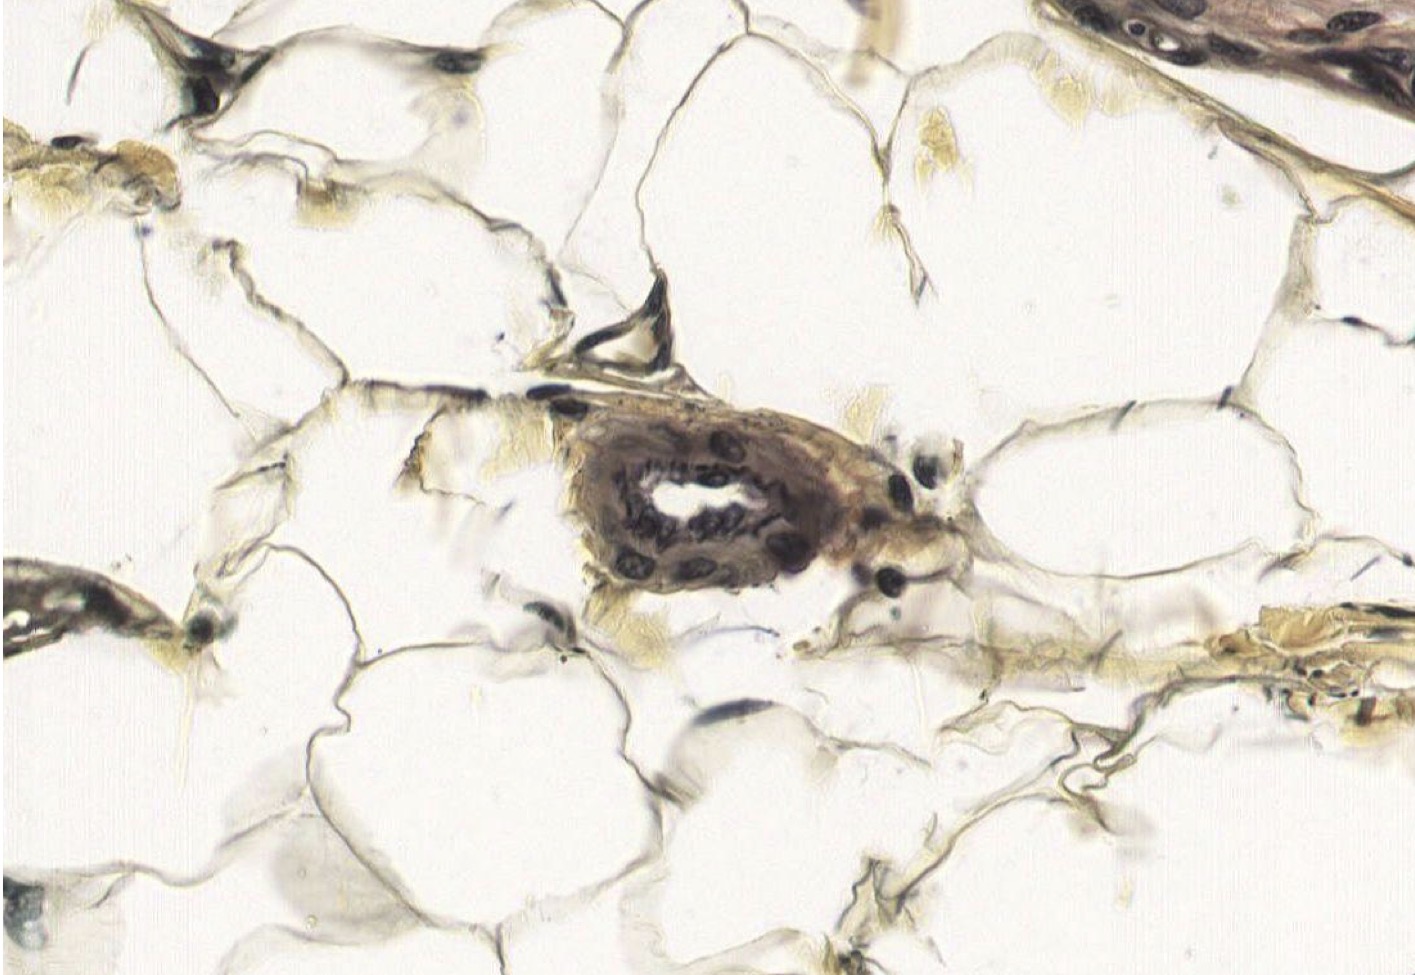

I = Epicardium in Ventricle.

Outer mesothelial (simple squam epit) cells missing, supported by DICT on outside and has Loose Unilocular Adipose CT.